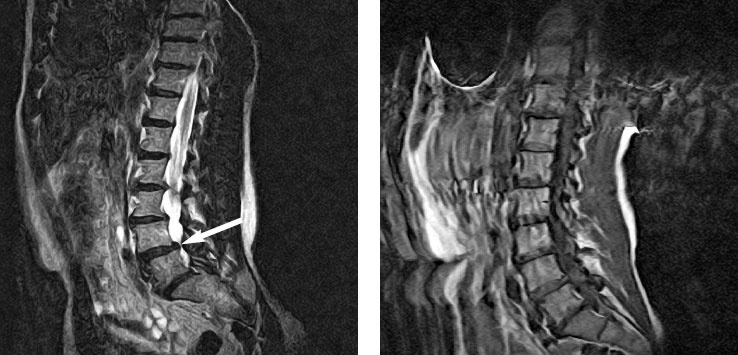

Рисунок 34. Обратите внимание, что спондилолистез (слева) не появляется на правом изображении. Силы, воздействующие на переднюю, заднюю и боковые поверхности позвонков в васиштхасане, значительно уменьшают спондилолистез. Это указывает на два момента: во-первых, йога способна выравнивать позвоночник; во-вторых, мышцы, прикрепленные к позвонкам, могут их двигать. Укрепление этих мышц будет оказывать на позвонки нагрузку, способную противодействовать остеопорозу.